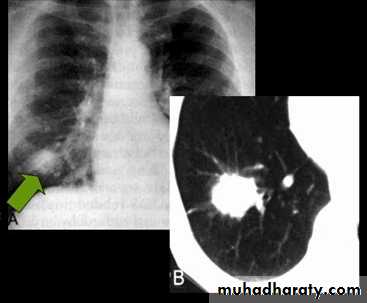

CAVITARY LESIONS ( lung abcess)

A PA chest radiograph demonstrates a thick-walled cavity with fliud level adjacent to heterogeneous opacities in the left upper lobe.Necrotizing pneumonias and abscess formation .

Ruptured H.C. With water lily sign .

Un complicated Hydatid cyst of th lung , cuased by echenococus granulosis seen as well defined nodule or mass lesion .

Early rupture is sen as a cresnt air sign .ddx aspergillus ball